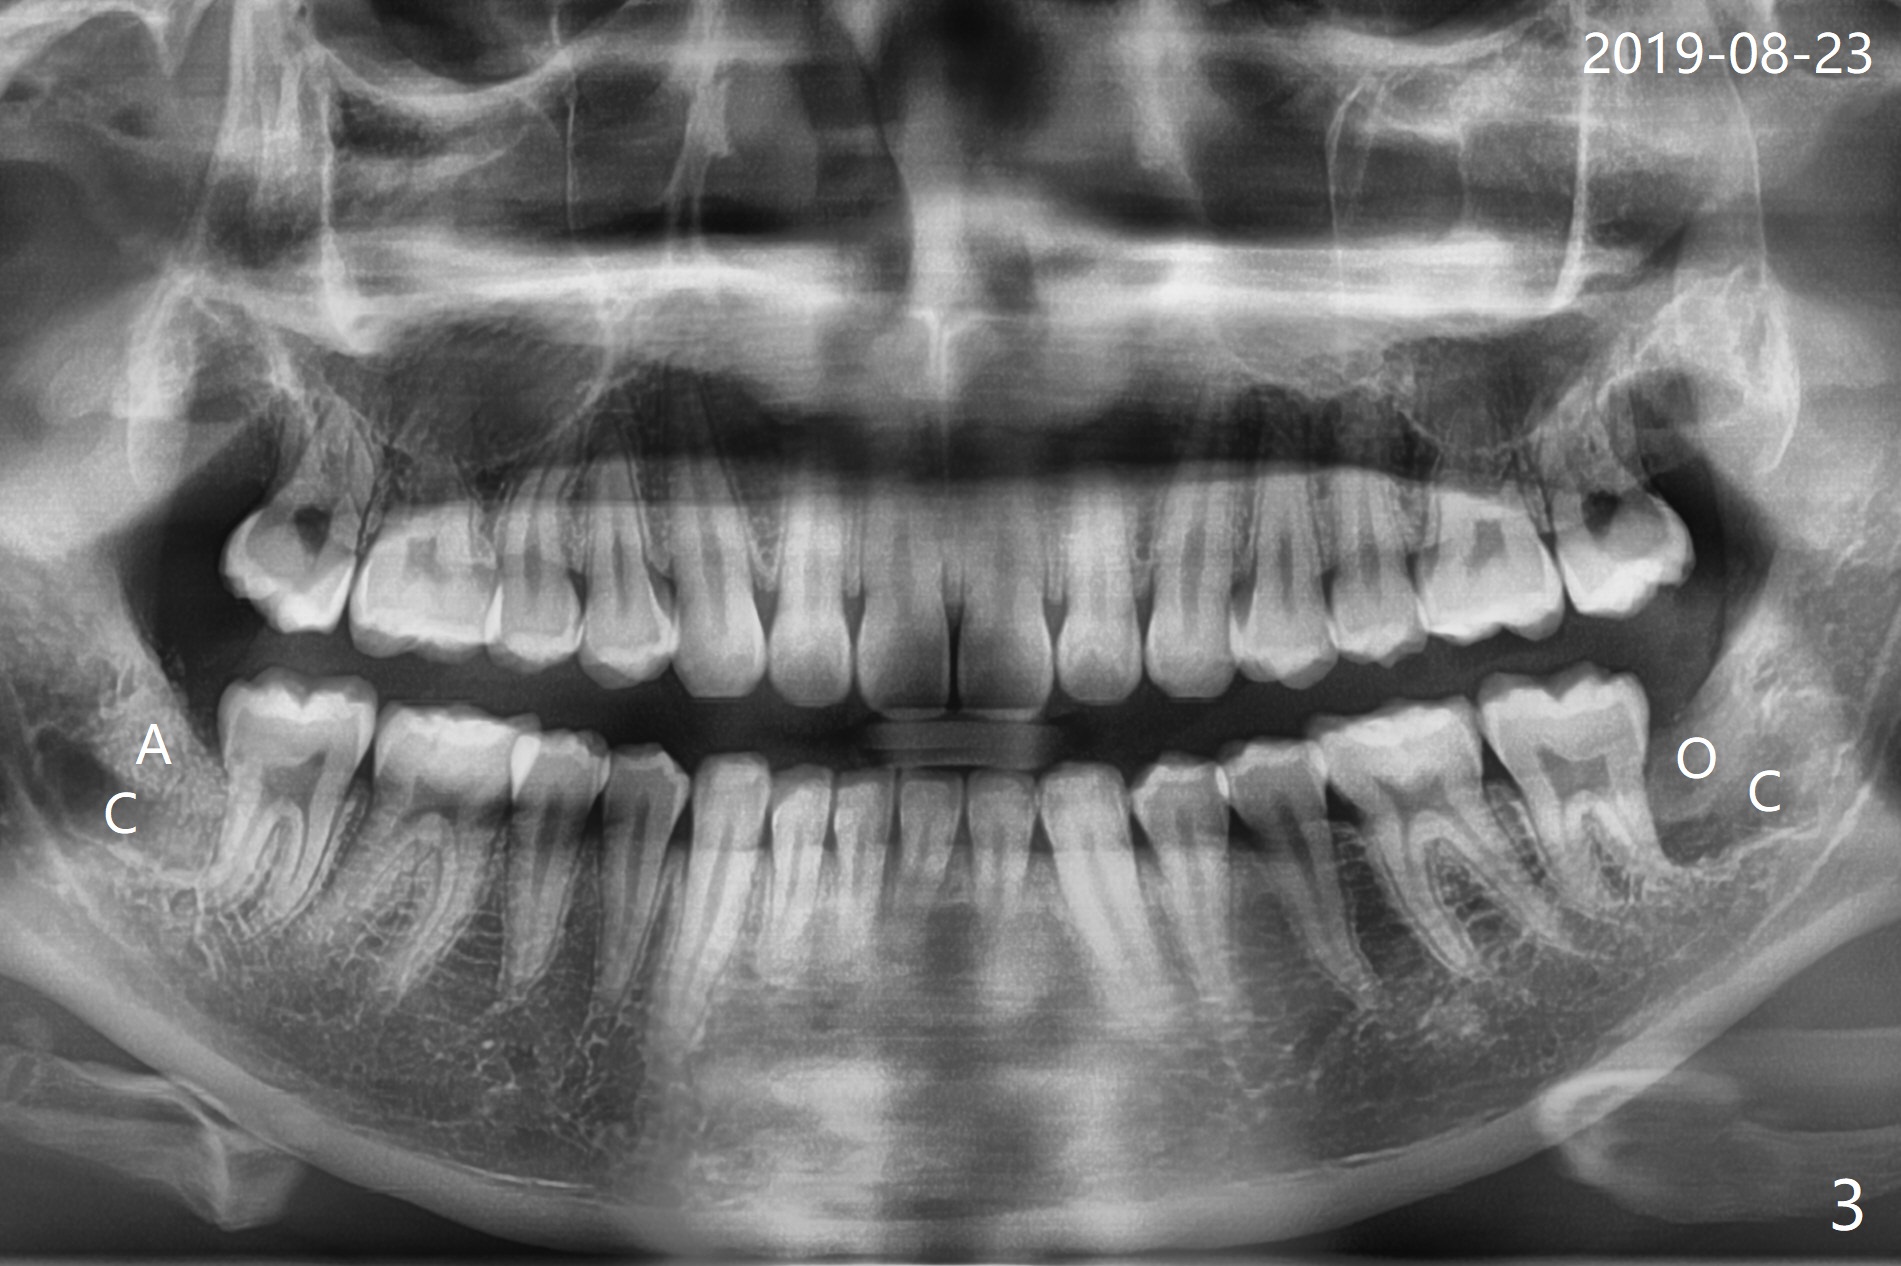

A 22-year-old man, asymptomatic, is going to have #1,16,17 and 32 extracted (Fig.1, fully bony impaction).  For the large lower sockets (actually Buccal Impaction), collagen plug (Fig.3 C) is placed in the inferior half, while Bone Cement (Bond Apatite from Augma (Fig.2,3 A)) and Osteogen plug (Fig.3 O) in the superior half at #32 and 17, respectively.  4-0 Chromic gut suture is used to close the wounds.  The four sockets heal (with increased bone density) 4 months postop (Fig.4).